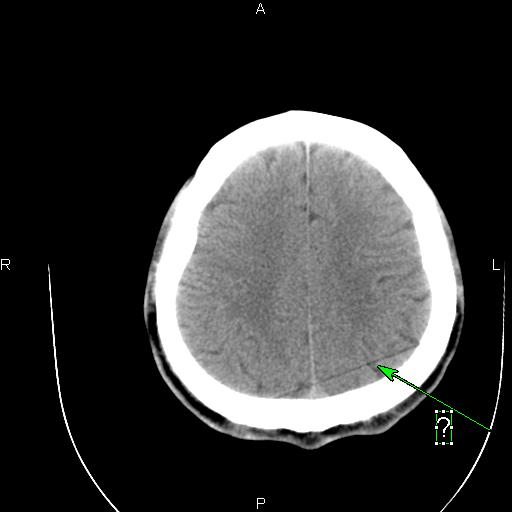

这种伪影是怎样造成的?怎样解决呢?